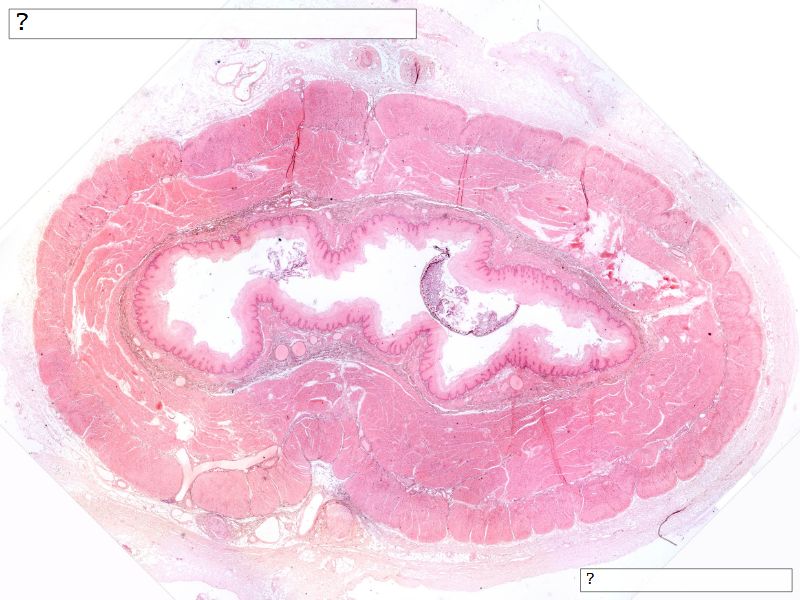

Fill in all the missing labels, and assess as you move through the slides. Answers on the down slide. It is important to do this using pen and paper, and not just glance through the images.